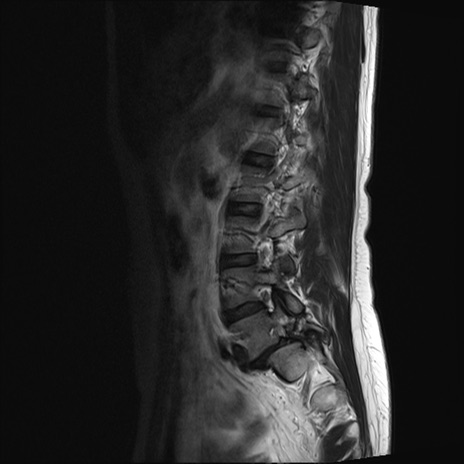

【整形】TIPS症例4 腰椎MRI T2WI(矢状断像)

腰椎MRI

T1WI(矢状断像)